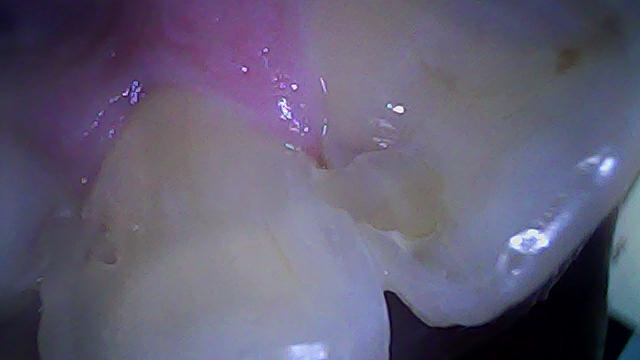

• 1번 째 사진